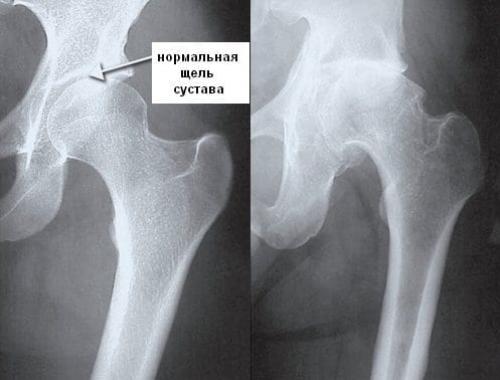

Разрушение тазобедренного сустава сначала происходит бессимптомно, поэтому больной не обращается к врачу. Только спустя несколько месяцев, а иногда и лет возникают первые признаки дегенеративно-дистрофического процесса. Появляются, усиливающиеся, отечность и. На этой стадии деструкции ТБС происходят уже необратимые патологические изменения хрящей, костей, соединительнотканных структур.

Разрушенная головка бедренной кости.

Чем раньше больной обращается к ортопеду, тем выше вероятность успешного консервативного лечения с помощью фармакологических препаратов, ежедневных, физиотерапевтических процедур. Пациентам с разрушениями тазобедренного сустава средней и высокой степени тяжести показаны артродез или.

Диагностировать патологическое разрушение тазобедренного сустава сможет только врач.

Так выглядит тазобедренный сустав, пораженный артритом.

Суставная жидкость при коксартрозе густая, вязкая. Изменение консистенцииприводит к высыханию поверхности гиалинового хряща, потери им гладкости и прочности. Появление на ней трещин становится причиной постоянного травмирования хрящей при движении, их истончения, усугубления патологических изменений в тазобедренном суставе. Затем начинают деформироваться кости, пытаясь «приспособиться» к увеличению на них давления. В результате ухудшается обмен веществ, провоцируя прогрессирование деструкции, а впоследствии — и атрофию мышц ноги.

Стадии развития коксартроза ТБС.

Динамика разрушения.